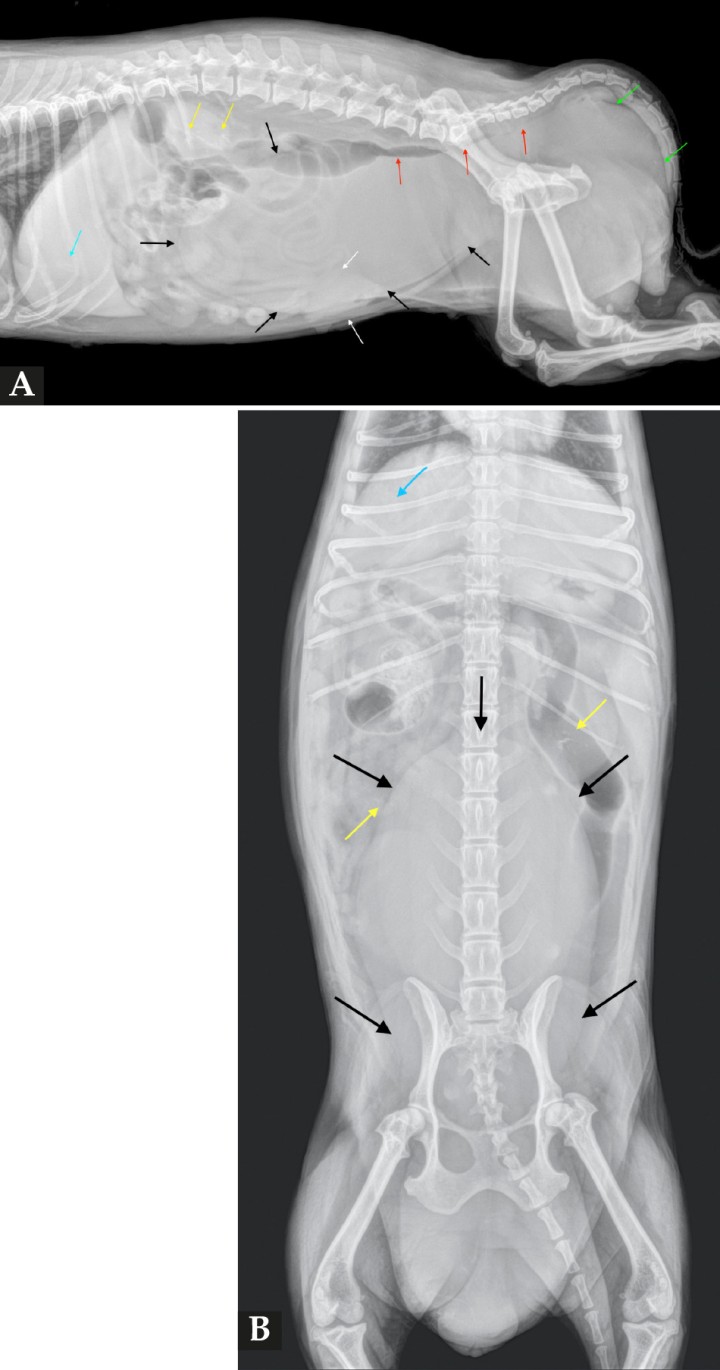

Se refiere una perra mestiza no esterilizada de 15 años de edad y 5 kg de peso, con tumefacción bilateral de la región perineal, de desarrollo progresivo en 72 h. El animal presentaba tenesmo y disuria. Los tutores refieren no tener constancia de descarga vulvar sanguinolenta visible durante el proestro/estro, no pudiendo determinar la fecha del último ciclo estral. La exploración física mostró una protuberancia perineal de consistencia depresible y dolorosa, así como un efecto masa en el abdomen a la palpación. La analítica sanguínea reveló leucocitosis 26 k/µl (5,05-16,76 k/µl), neutrofilia 23,33 k/µl (2,95-11,64 k/µl), monocitosis 1,32 k/µl (0,16-1,12 k/µl); fosfatasa alcalina elevada 424 U/l (10-125 U/l) y GGT elevada 13 U/l (0-11 U/l). Se realizaron radiografías de la cavidad abdominal (Fig. 1).

<p>Radiografías de la cavidad abdominal de una perra mestiza de 15 años de edad. (<strong>A</strong>) Radiografía lateral derecha. (<strong>B</strong>) Radiografía ventrodorsal.</p>

Radiografías de la cavidad abdominal de una perra mestiza de 15 años de edad. (A) Radiografía lateral derecha. (B) Radiografía ventrodorsal.